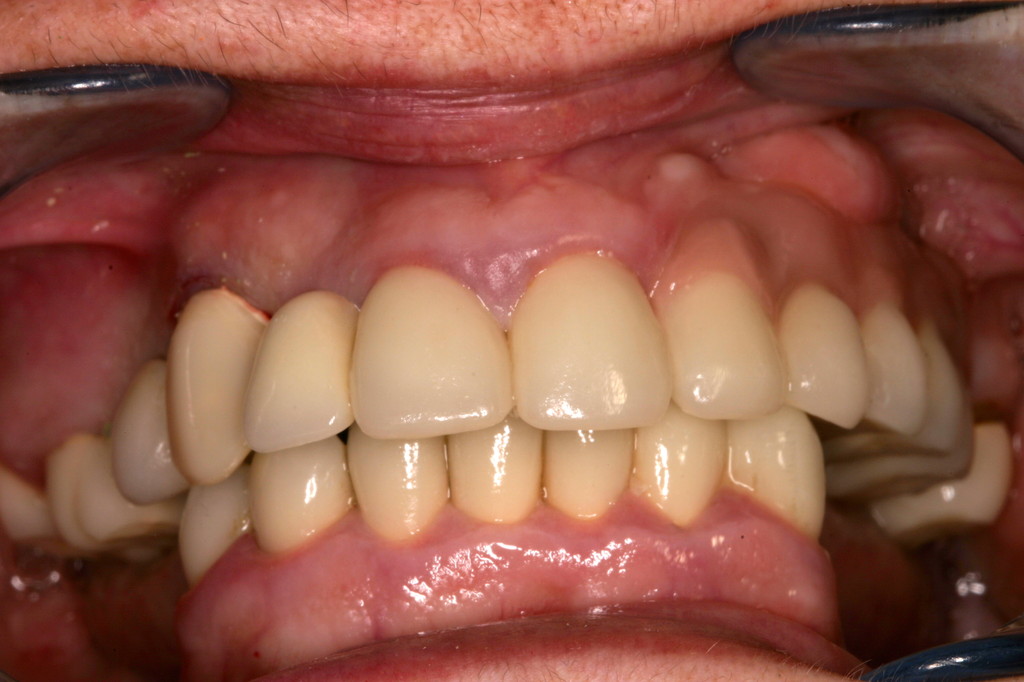

REHABILITACIÓN CON IMPLANTES Y CIRUGÍA PLASTICA PERIODONTAL.

REHABILITACIÓN CON IMPLANTES SIN CIRUGÍA.

REHABILITACIÓN IMPLANTOSORTADA EN MANDÍBULA Y MAXILAR.

REHABILITACIÓN ESTÉTICA CON IMPLANTES.